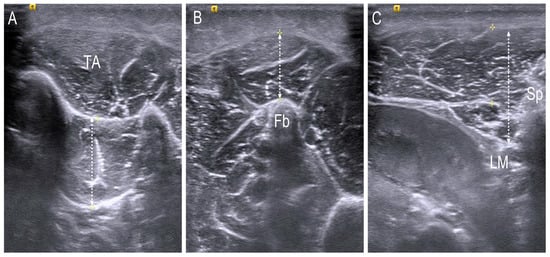

For obtaining the image of the tibialis posterior (TP) and peroneus longus (PL), the participants were asked to sit on the edge of a bed with flexed hip and knee positions. The images of the TP muscle as the inverter of the foot and the PL muscle as the evertor of the foot were obtained in a transverse view, and the length of each muscle was measured by using a measuring tool set on the ultrasound device. The scanning sites were based on the previous study [20] and were as follows: for the TP, one-third point of the imaginary line connecting from the medial malleolus and tibial tuberosity; for the PL, one-half point of the imaginary line connecting from the lateral malleolus to tibial tuberosity. Anterior–posterior measurements from the aponeurosis to the deepest fascia of the TP and from the superficial fascia of the PL to the bony surface of the fibula were executed, respectively. To obtain the image of the L1 multifidus, patients were asked to lay on their stomach with the forehead resting just above the breathing hole in the plinth, the head in the midline, and the arms outstretched. One pillow was placed under the hips to eliminate the lumbar lordosis [21]. The scan point was over the L1 multifidus next to the landmark of the L1 spinous process in a transverse plane and the distance between the muscle fascia below subcutaneous tissue and lamina was measured with the linear measuring tool (Figure 4). The muscle thickness was measured three times, and the mean value was used.

Figure 4.

Anterior–posterior measurement of (A) tibialis posterior muscle; (B) peroneus longus muscle and (C) L1 Multifidus in the transverse scan. TA; tibialis anterior, Fb; fibula, LM; lamina, Sp; spinous process.